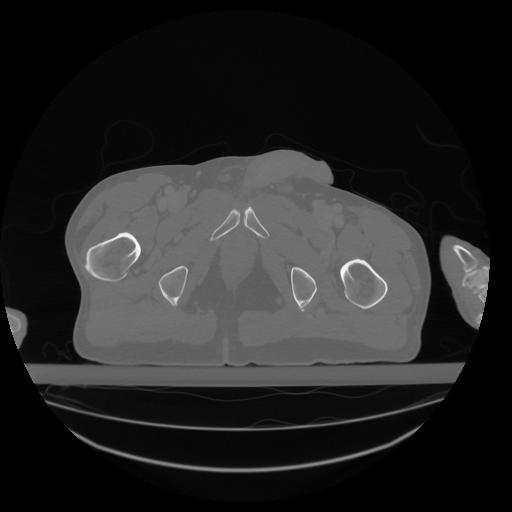

34 CUERPO,CE,Vol,1.0,CUERPO,,